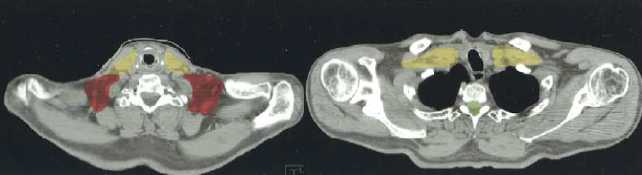

(a–l) Marked lymph nodes (LNs) with each LN group separated by color.

yellow, jugular LN (II, III, IV);

red, spinal accessory LN (V);

G    Thyroid gland                                                                           Superior limit of thyroid gland    Inferior limit of thyroid gland

H    Apices of lungs, clavicles                                                                  Apex of lung    Head of clavicle